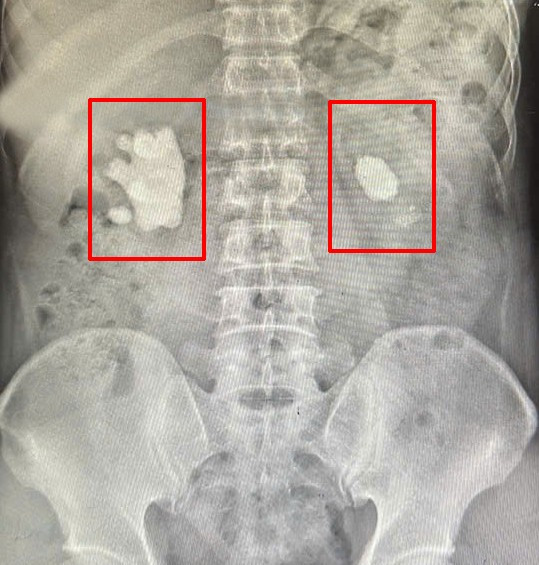

Hai viên sỏi san hô trên phim chụp - Ảnh BVCC

Tại bệnh viện, kết quả chụp Xquang và Cắt lớp vi tính (CT Scanner) cho thấy người bệnh có sỏi thận 2 bên, thận bên phải có khối sỏi lớn hình dạng giống san hô chiếm gần hết bể thận.